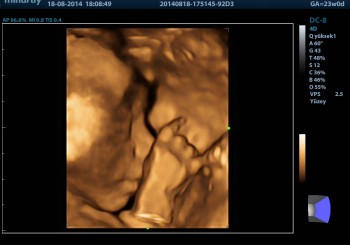

Ayrıntılı Gebe Ultrasonu Ayrıntılı Gebe Ultrasonu bebeğin organlarının gelişiminin büyük ölçüde tamamlandığı, amniyotik sıvının nispeten fazla olması nedeniyle görünebilirliğinin arttığı ve böylece organların nispeten daha detaylı olarak görülebildiği gebeliğin 18 ila 23. haftaları arasında genellikle Radyoloji Uzmanı Doktorlar tarafından uygulanan bir incelemedir. Ayrıntılı Gebe Ultrasonu Sırasında Bebek Ayrıntılı Biçimde İncelenir Ayrıntılı Gebe Ultrasonu sırasında annede meydana gelmiş...